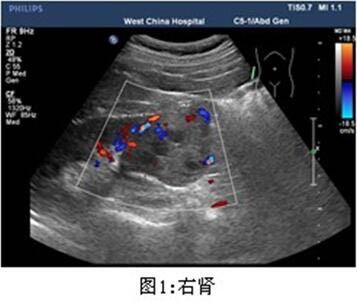

查体无特殊。 辅助检查: 泌尿系彩超示:右肾下极稍高回声团,大小约4.7*4.4cm,边界尚清,内回声不均质。

患者泌尿系彩超发现右肾下极稍高回声团,大小超过4cm,考虑肾错构瘤可能,手术切除指证明确,遂行腹腔镜右肾部分切除术。